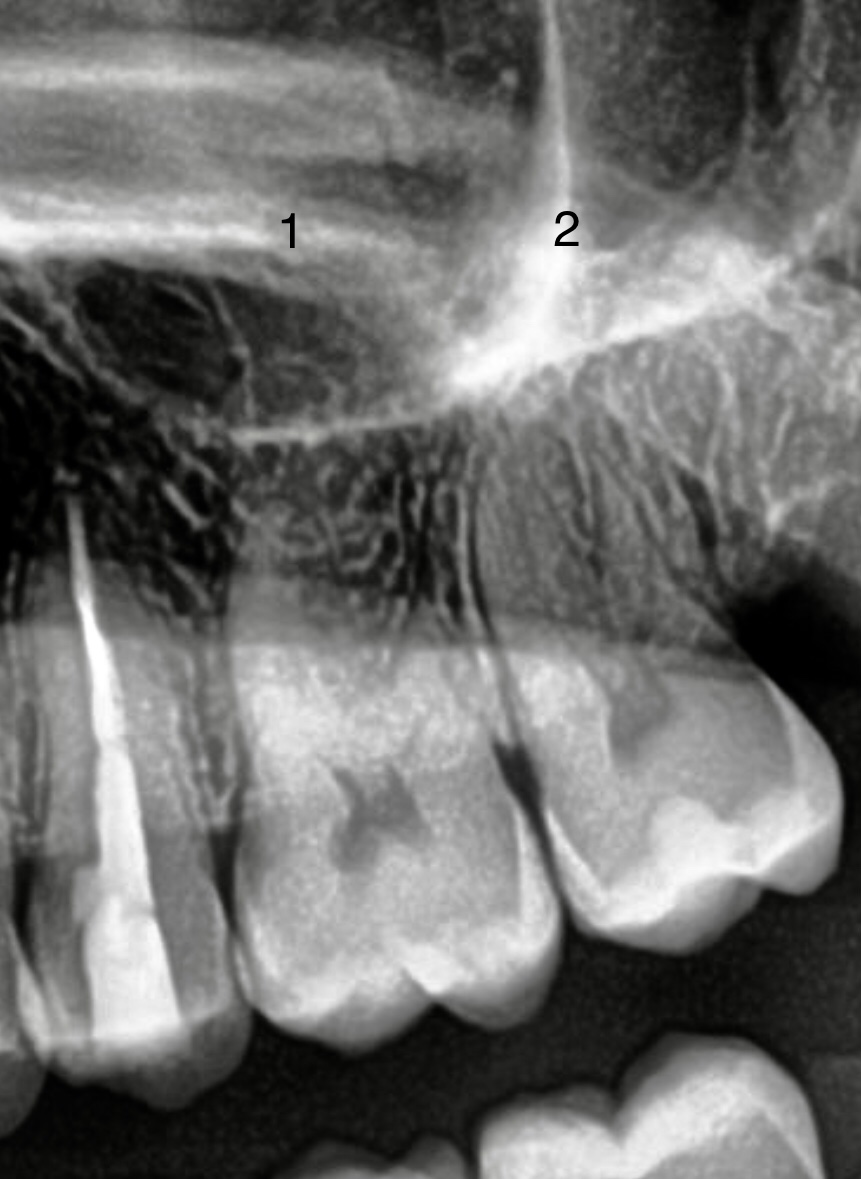

Ik heb twee foto’s toegevoegd. Op de röntgen foto heb ik de nummers 1 en 2 toegevoegd. 1 staat voor de kies met een breuk en 2 voor de kies met een vulling.

Nr 1 is de kies met scheur??. Is dat een barst in een kies zonder vulling of is dat de rand v e vulling?.(eerste foto).Als rand v e vulling dan glad maken en beoordelen als een barst dan zou ik een vulling maken .

Klopt, nummer 1 is de kies met scheur. Het is een barst zonder vulling. Het zit tussen de twee behandelde kiezen.

Bij de derde kies met WKB, was er eigenlijk niets aan de hand. Dit was nog een goede kies alleen vanwege zoveel pijnklachten is het behandeld. (Het puntje van de WKB-vulling steekt een puntje uit boven de wortel is mij verteld.

Al om al is de pijn in het gebied van de drie kiezen niet weg en het was zo moeilijk te pijlen waar het nou afkomstig is. Maar ik voel de meeste pijn bij de kies met een scheur (nr1) en ook bij kies met vulling (n2), daar wat minder. De kies met WKB is gevoelig, maar ik vermoed dat het gevoelig is door de kies met een vulling, omdat het daar het meest pijn doet.